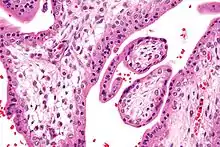

Micrograph showing chorionic villi. Very high magnification. H&E stain.